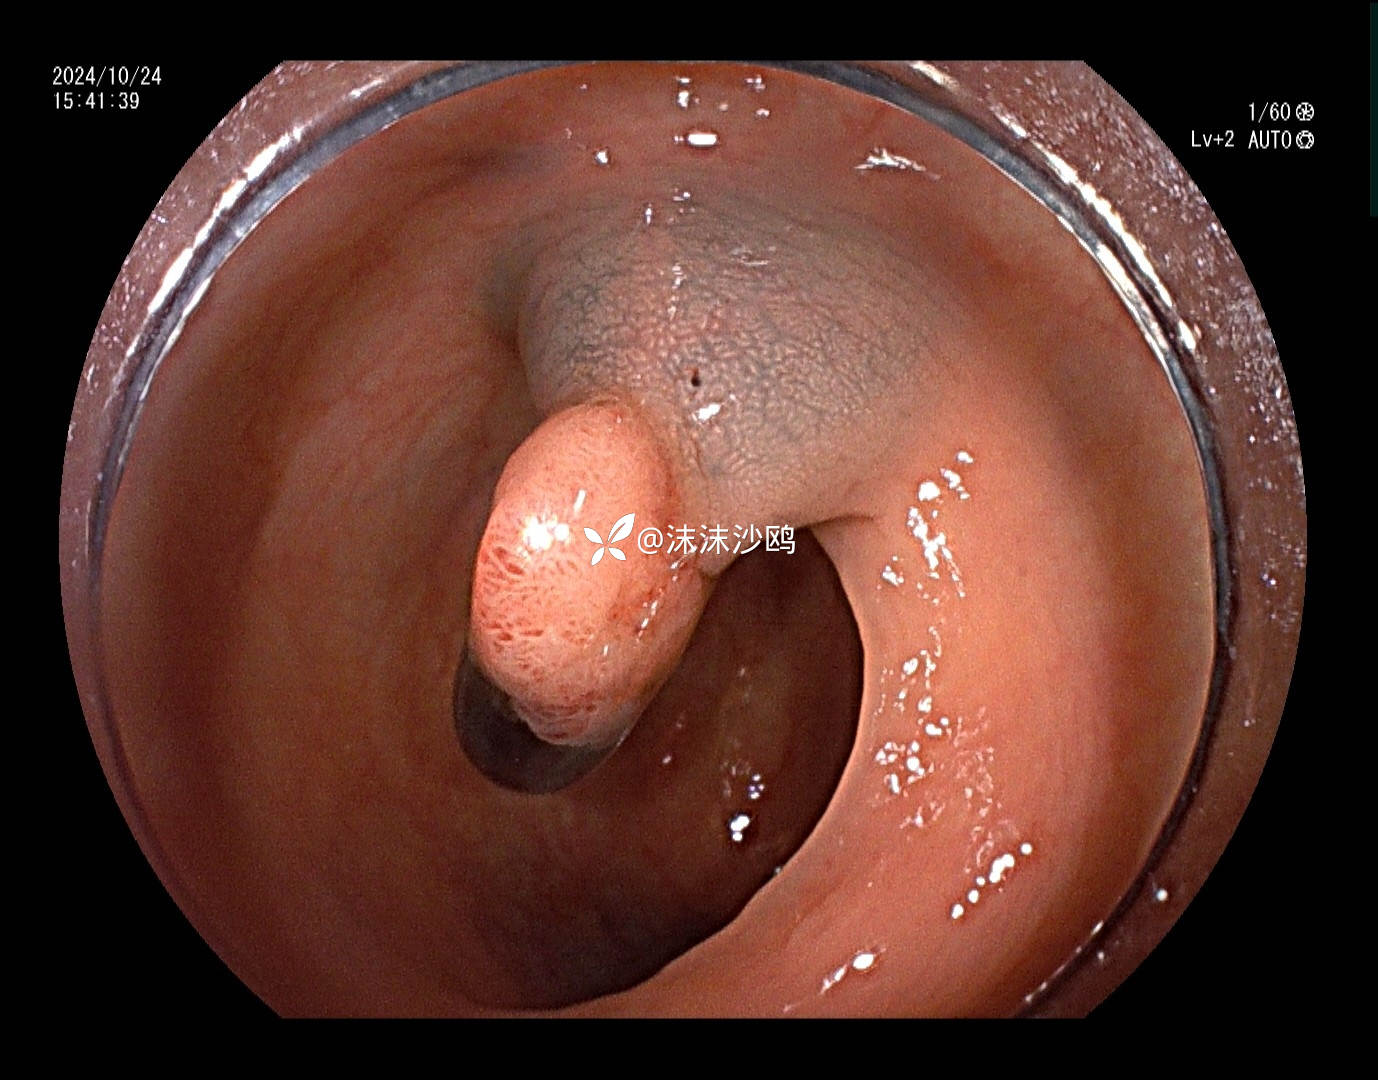

患者去年发现乙状结肠肿瘤同是发现多发腺瘤样隆起,先做了肿瘤切除手术,没有进一步放化疗,现来复查肠镜顺便嘎息肉。翻看之前的肠镜报告,肠道清洁差,发现的息肉就有六七个,应该还有漏掉的。嘱患者肠道一定要清洁到位。今日下午只安排了他一个人的肠镜专场,专门处理他的息肉。

冰山一角,大大小小嘎了十三四个,大的就有六七个,大部分EMR切除。希望术后不要有并发症。